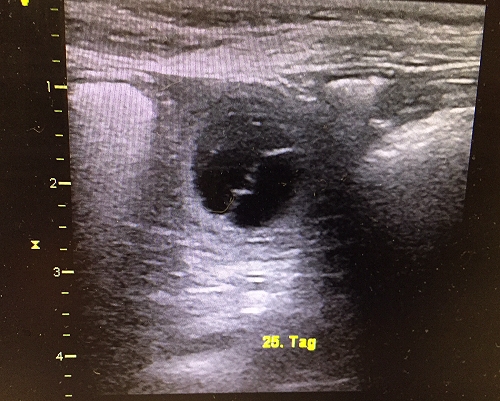

Wir sind unbeschreiblich glücklich 😀 Denn heute durfte Kaami einen kleinen Ausflug mit mir zu meiner Arbeitsstelle unternehmen und wurde geschallt – das Ergebnis: Kaami ist tragend! Wir freuen uns daher auf kleine „Skaamis“ im Juli 2017. Checkt unsere Welpenseite hier!

Nun brauchen wir viele Daumendrücker, dass der Rest der Trächtigkeit weiter problemlos verläuft und im Juli alle Welpen gesund auf die Welt kommen.